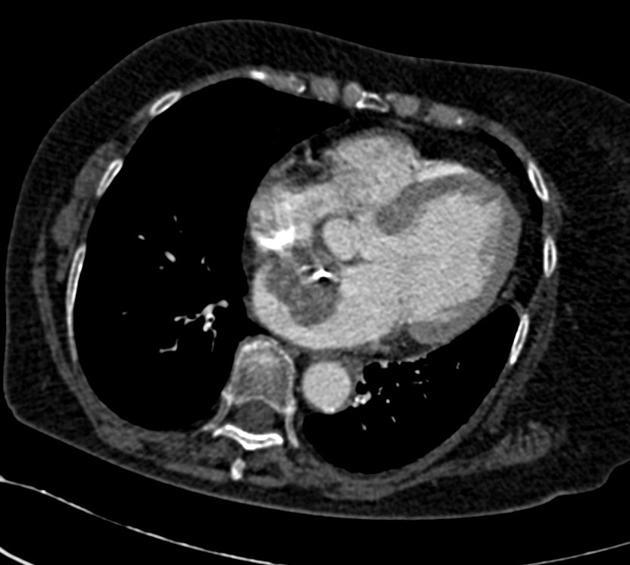

CT

Myxomas, as is the case with other cardiac tumors, appear as intracardiac masses, most often in the left atrium and attached to the interatrial septum. They are usually heterogeneously low attenuating (approximately two-thirds of cases 2,8). Due to repeated episodes of hemorrhage, dystrophic calcification is common 8.

If the mass is pedunculated, the motion within the heart can be demonstrated, including prolapse through the mitral valve.

MRI

MRI appearances are heterogeneous, reflecting the non-uniformity of these masses. They are typically spherical or ovoid masses which may be sessile or pedunculated 2,3.